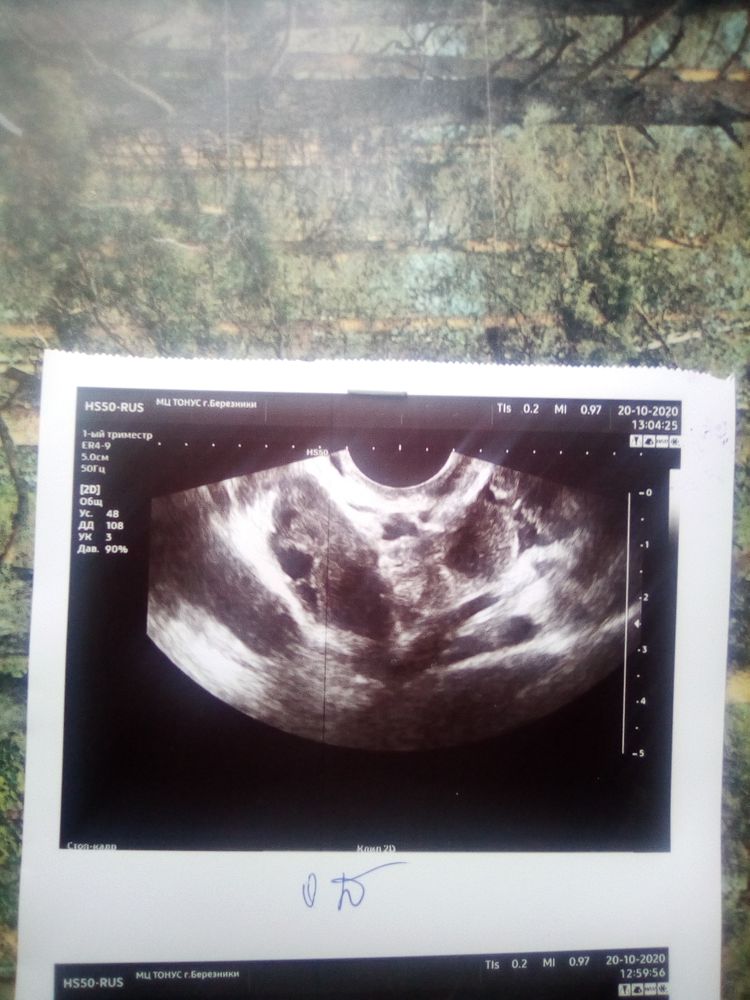

Добрый день ,сделали снимок УЗИ,но я не разбираюсь и ничего не понимаю что это и что на нём,кто то может разбирается что это,помогите пожалуйста?

здравствуйте ситуация такая 8 октября решила сделать тест на беременность оказался + ,9 октября пошла кровь,длилось это 4 дня и прекратилось,12 октября пошла на узи ничего нет,сдала хгч 756-19 октября,пошла снова на узи 20 октября ииии опять ничего.....22 октября хгч 768......что это помогите пожалуйста,была у гинеколога сказали мол что то было но вышло такбывает,тест положительный с 8 октября по сегодняшнее число 30 октября,фото прилагается(((((((((((((((((